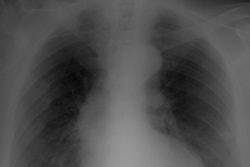

The institution's protocol was to perform a single postoperative Grashey anteroposterior-view x-ray of the shoulder in the postanesthesia care unit, with follow-up radiographs at two weeks, six weeks, four months, and one year after surgery. All images were interpreted by a musculoskeletal radiologist; clinical notes were reviewed to see if the images resulted in a change in patient management.